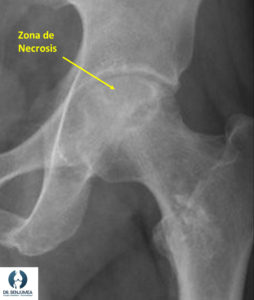

Los síntomas más habituales de la necrosis son padecer dolor en la ingle, que aumenta o bien por la noche o bien cuando plantamos peso en la pierna afectada. Cuando la lesión evoluciona y sobre todo si la articulación se ocupa de líquido o sufre degeneración, el dolor puede incrementarse con cualquier movimiento e incluso la cadera perder movilidad. Ante la sospecha, se deben realizar tanto radiografías como una resonancia magnética de la cadera afectada.

La radiografía nos servirá para ver el estado general de la articulación, por si ya hubiera artrosis, lo que influye enormemente en el tratamiento como luego veremos. En la resonancia podremos ver el estado evolutivo de la lesión y la zona afectada.